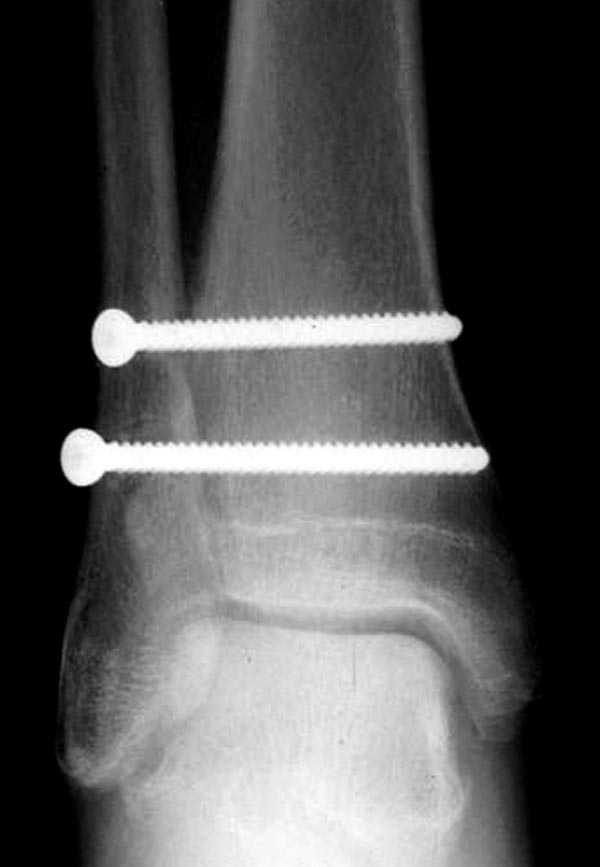

Невозможно устранить проблему фиксацией малоберцовой пластиной или другими методами, потому что главная проблема - разрыв межберцовой мембраны, которая находится между костями и внизу в голеностопе в синдесмозе.

Две параллельных шурупа создают условия для сращения мембраны и синдесмоза, 8 недельный срок достаточен, и можно удалить фиксаторы.

Без оперативного лечения Межкостная мембрана будет источником боли у спортсменов.